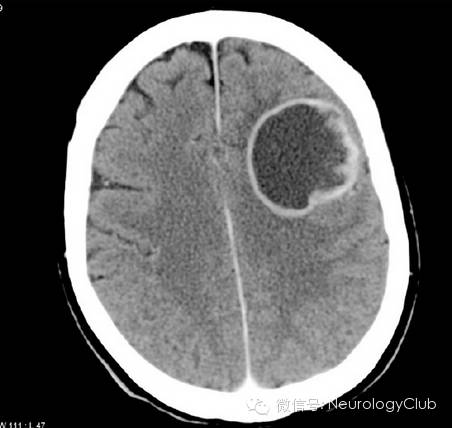

CT显示肿瘤呈边界不清的混杂密度影,常见瘤内出血所致高密度或囊性变、坏死;肿瘤跨胼胝体生长至对侧大脑半球时,呈“蝴蝶征”,水肿和占位效应明显。MRI在一定程度上能够揭示肿瘤的病理改变:T1WI呈不均匀低信号(图 1a),多合并坏死、囊性变或出血性改变;T2WI呈混杂高信号,中心坏死区为高信号,肿瘤生长区周围呈等信号,部分病变与肿瘤周围水肿分界不清,肿瘤内异常血管增生形成线样“流空效应”区(图 1b)。增强扫描肿瘤边缘呈显著对比强化,呈“花环”(ring/rim-enhancing)样(图 1c)、不规则环形、岛形或螺旋形改变;囊变性和坏死区周围肿瘤实质呈特征性“假栅栏征”,即圆形、椭圆形未强化区散在分布在强化区内,类似乳突蜂窝小房。DWI多呈高信号,ADC值明显减低。MRS提示NAA峰降低,Cho升高明显,MI峰较低级别星形细胞瘤低。灌注成像显示,病灶周围和病灶内有多处高灌注区(图 1d),提示大量肿瘤血管生成。胶质母细胞瘤虽具典型影像学特征,但仍需注意与颅内单发转移瘤、间变性胶质瘤、淋巴瘤等肿瘤性病变,以及脑脓肿、结核瘤、脱髓鞘假瘤等非肿瘤性占位性病变相鉴别。

(图6:CT环形强化)